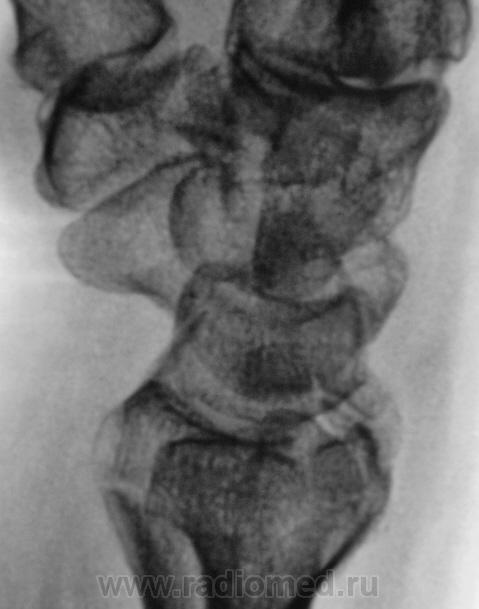

Контур нечеткий, склероз и т.д.-на перелом не схоже. А действительно локальная болезненность в латер. лодыжке?

Да, болезненность есть, клинически хирурги - за перелом.

Краевой перелом Наружной лодыжки